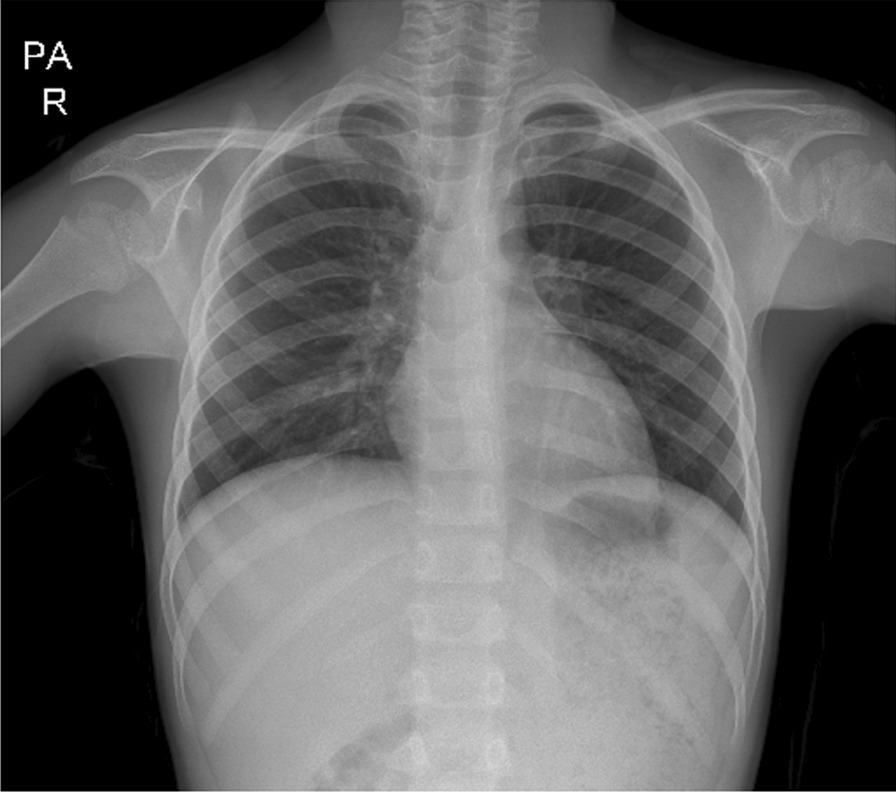

After surgery, the patient was stable, and hydration and antibiotic therapy were continued. Pantoprazole was administered to prevent stress ulcers. Two days after surgery, the NG tube was removed and liquid diet was started. Incentive spirometry and chest physiotherapy were initiated to rehabilitate pulmonary function. The patient was discharged home uneventfully, and follow-up visits after 3 months showed no complications (Fig. 5).

Fig. 5.

CXR of the patient 1 month after surgery